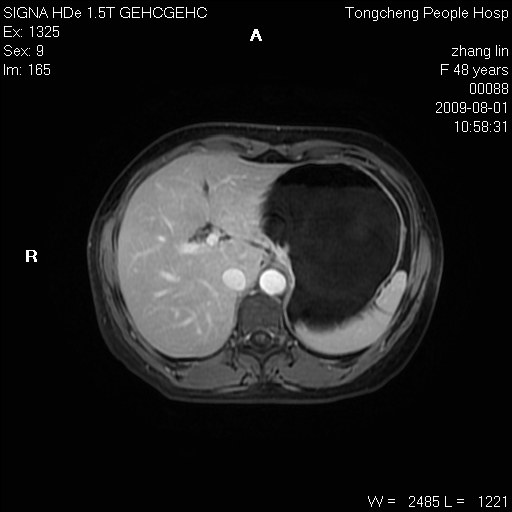

女,48岁。健康体检,彩超发现右肾占位性病变。平素健康。

临床诊断:右肾占位性病变,性质待定(囊肿?肿瘤?)。

上中腹部mr平扫+增强扫描,图像如下:

右肾上极见一类圆形病灶,t1wi呈等信号t2wi呈等高混杂信号,三期增强无强化,边界清---考虑囊肿出血。

同反相位均表现为等信号,病变无强化,考虑含蛋白的囊肿可能,弥散加权相或许有些帮助,

慢性胆囊炎